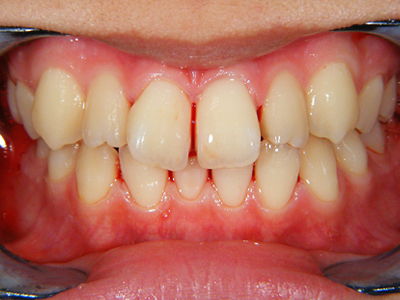

11. 術後正面

矯正装置による動的移動を終え、ブラケットを除去して歯冠研磨した後の正面写真です。ブラケット装着期間は約2ヶ月強。その間は毎週来てもらいました。もちろん早ければ良いというわけではなく、無理な歯牙移動はさまざまな弊害をもたらします。後は可徹式の保定装置を作製します。